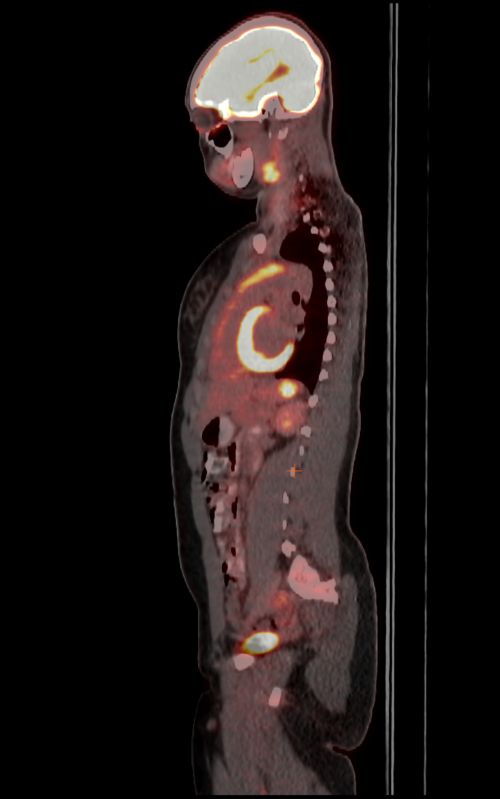

Psma Pet Ct Accurately Detects Prostate Cancer Spread Nci

Psma Pet Scan Demonstrating Location Of Lesion On The Right Anterior Download Scientific Diagram